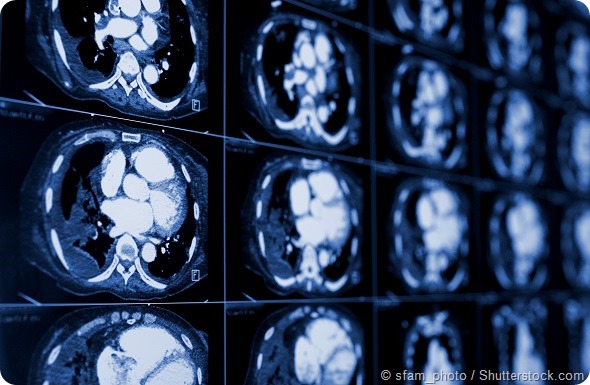

computed tomography of the chest. Medical background. monochrome photos